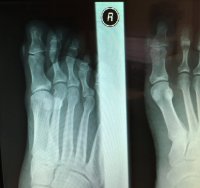

Fast forward to last month. I backpacked 12 miles and it started hurting like crazy. Whatever was in there was right under the skin and I could actually move it around a bit. So I go to my doc and he x-rays it. The radiologist report just said "12mm foreign object with the same density as bone". My report was "That looks like a catfish barb!".

But this would be lame without photos. For those that don't want to see photos of my x-rayed foot as well as a freshly removed chunk of catfish barb from my toe (a little blood), then don't click below to see the photos. Everyone else, proceed.

xray-full.jpg

xray-zoom.jpg